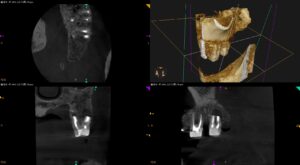

左上奥歯が腫れて痛い…〜#15 Apicoectomyか?Intentional Replantationか?その臨床的判断方法にCBCTは有効的

紹介患者さんの治療。 主訴は、 左上奥歯が腫れて痛い… である。 歯内療法学的検査(2025.4.4) #14 Cold N/A, Perc.(-), Palp.(-), BT(-), Perio Probe(WNL), … 続きを読む 左上奥歯が腫れて痛い…〜#15 Apicoectomyか?Intentional Replantationか?その臨床的判断方法にCBCTは有効的